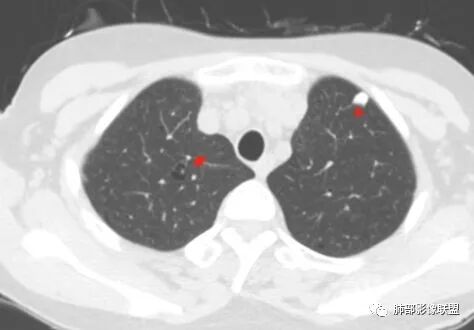

胸CT:1.双肺多发囊性变,以中下肺为主,病变边缘可见肺动脉,部分囊内可见分隔及肺动脉,双下部分肺野周围可见小叶中心结节及树丫征。

2 左肺上叶尖后段 右肺上叶前段 右肺下叶外基底段 结节影,边界清楚,可见柔软毛刺,左肺下叶后基底段混合密度影。

1.左下肺腺癌;2.两肺弥漫性病变(多发囊腔、部分囊壁不规则,分布无特异,结节,空洞,树芽征,GGO),结合眼部情况首先考虑LIP,不典型感染(病毒或其他)待排。

双肺多发囊性病变,右下肺结节伴树芽,左上肺结节影,边缘清晰,毛刺。有类风湿,及眼干病史。考虑lip,腺癌。鉴别血管炎。

常规分析:右眼红疼1天,滴眼史两年,有类风湿病史,考虑有干燥综合征(SS)可能,需要了解自免抗体检测情况,双肺囊变需要考虑LIP,另右上叶前段GGO要鉴别腺癌或转移可能,右下叶背段多发树芽改变,双肺多发实性小结节,结核?左下肺混合性GGO考虑侵润性腺癌可能,双侧胸膜下多发结节,部分合并GGO改变,右侧腋窝及纵隔淋巴结多见,转移?最后问题来了,这个病人一元(腺癌合并转移,包括整个囊变,实性结节,胸膜下都是转移)?二元(LIP合并腺癌伴转移或者淀粉样变基础上的LIP)?三元(LIP+结核+腺癌伴转移)?